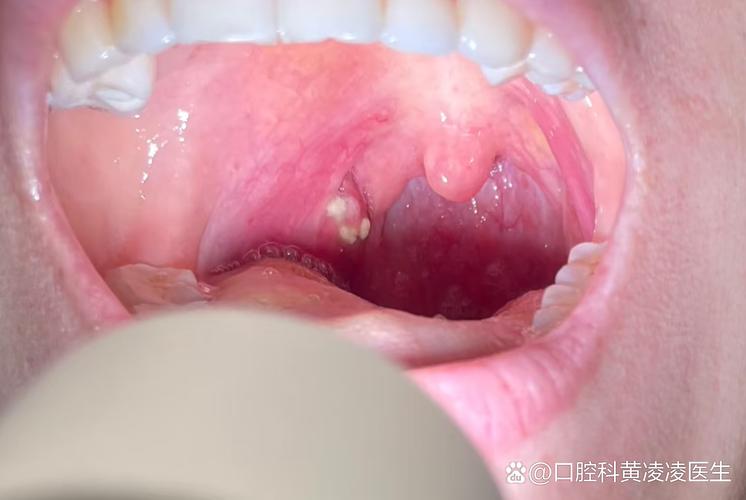

- 鹅口疮(Thrush):由白色念珠菌引起的真菌感染,特征是口腔黏膜上出现白色、像牛奶凝块一样的斑点或斑块,不易擦掉,擦掉后下方会发红、甚至出血,通常没有明显疼痛,但严重时可能影响进食,在婴幼儿中比较常见。

- 疱疹性口炎(Herpetic Stomatitis):由单纯疱疹病毒引起,初期可能只是牙龈和口腔内壁出现一些红色的小颗粒或丘疹,很快会发展成成簇的小水疱,水疱破溃后形成溃疡,孩子会因此疼痛、拒食、流口水、发烧。

- 手足口病(Hand, Foot, and Mouth Disease):由肠道病毒引起,除了手、脚、臀部出现皮疹外,口腔内也会出现疱疹或溃疡,初期可能表现为红色的小点或丘疹,很快变成疱疹,破溃后形成溃疡,孩子会非常疼。